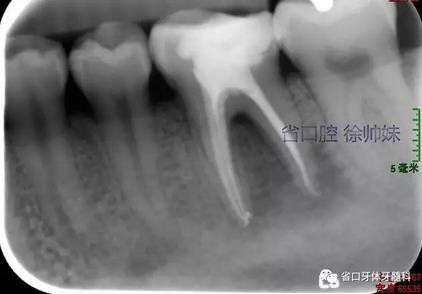

處理:36橡皮障隔濕,顯微鏡下去除封藥,沖洗根管,超聲蕩洗,熱牙膠連續(xù)波加壓充填根管(AH-PLUS),玻璃離子墊底,自酸蝕粘接,納米樹脂充填,調(diào)合,拋光。頰側(cè)牙周袋內(nèi)沖洗,置牙康。根尖片(圖3)顯示恰填,囑勿用患牙咬硬物,定期復查。

圖3 根充片